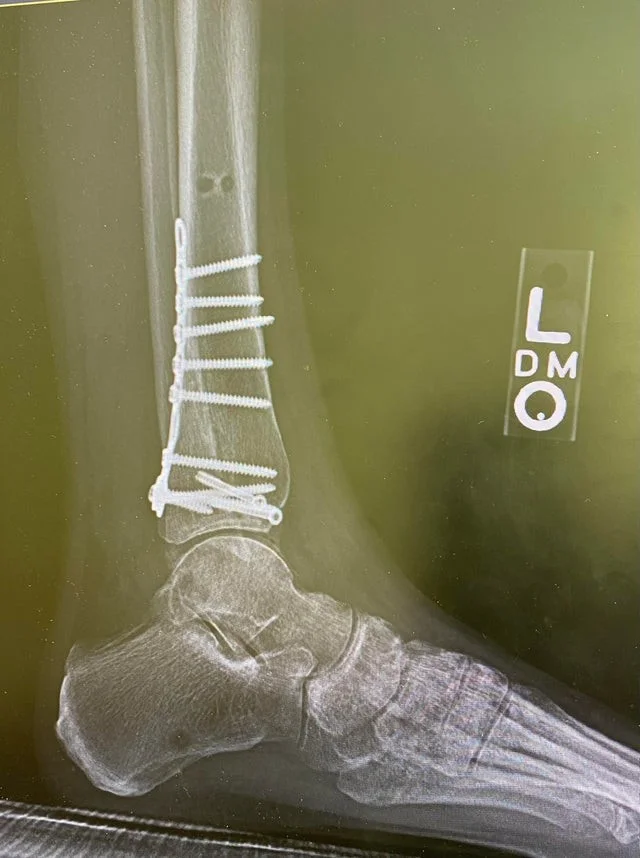

"Я упал в прошлую пятницу"